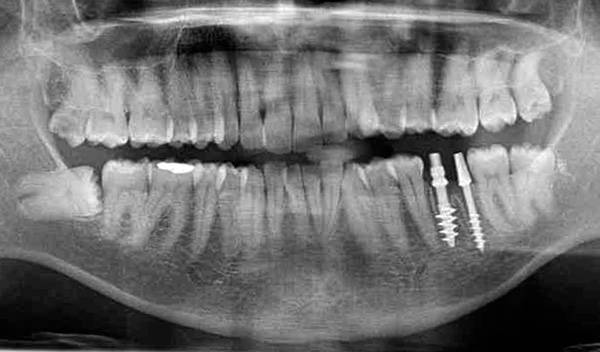

Le fotografie seguenti mostrano un esempio corrispondente (posizionamento di un impianto al posto di un dente estratto dopo la guarigione di un foro):